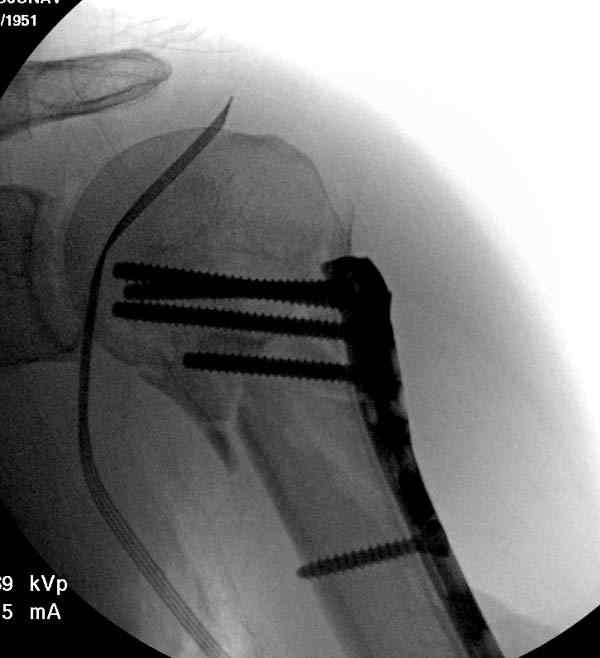

Рентгенограммы действительно с дефектом укладки, но интраоперационная репозиция, можете поверить, была удовлетворительная как в акcиальной, так и в сагиттальной плоскостях. Интраоперационная рентгенограмма прилагается, хотя укладка тоже на ахти. По тактике - разделяю Ваше мнение об отсутствии необходимости реостеосинтеза, а тем более об эндопротезировании, хотя это все было предложено пациентке ведущими ортопедами-травматологами России.

Здесь пример открытой репозиции 57 летнего с переломом плеча (1,2) смещение обнаружено на интероперационном снимке. При нормальной прямой проекция (3) угловое смещение обнаружили в аксиальной проекции (4)

После устранения смещения пластина установлена выше (5,6,7) и финальные снимки (8,9,10)